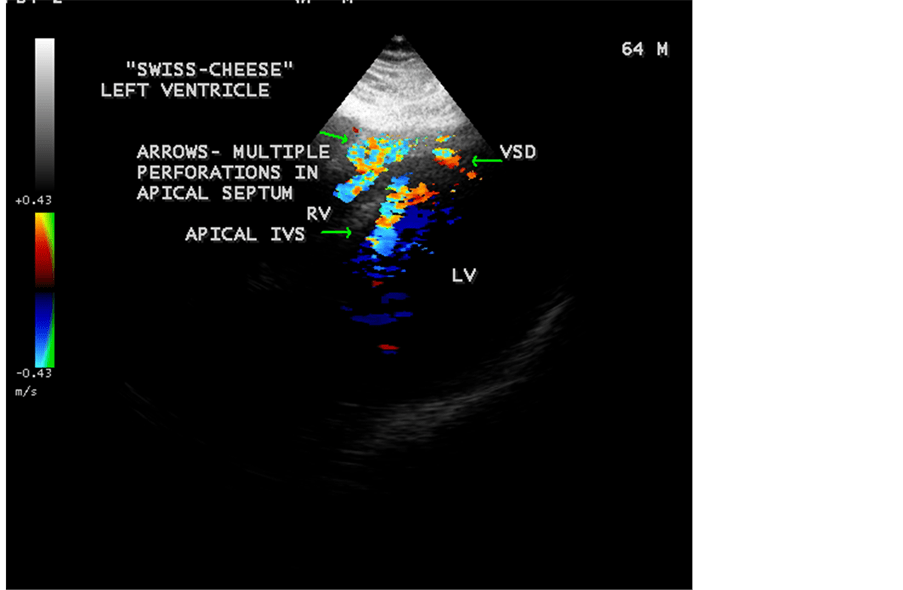

“SwissCheese” Left Ventricle in Acute Myocardial Infarction—A Case Report Swiss Cheese Vsd This examination showed multiple small, tubular defects in the ventricular septum. When used in conjunction with traditional patch repair, tar minimizes the amount of patch material requiring, thereby reducing septal dysfunction. “swiss cheese” defects are defined as the presence of uncountable vsds in the trabecular septum. “swiss cheese” ventricular septal defects (vsds) is a rare and most serious form. Swiss Cheese Vsd.

“SwissCheese” Left Ventricle in Acute Myocardial Infarction—A Case Report Swiss Cheese Vsd When used in conjunction with traditional patch repair, tar minimizes the amount of patch material requiring, thereby reducing septal dysfunction. “swiss cheese” defects are defined as the presence of uncountable vsds in the trabecular septum. This examination showed multiple small, tubular defects in the ventricular septum. “swiss cheese” ventricular septal defects (vsds) is a rare and most serious form. Swiss Cheese Vsd.

“SwissCheese” Left Ventricle in Acute Myocardial Infarction—A Case Report Swiss Cheese Vsd “swiss cheese” defects are defined as the presence of uncountable vsds in the trabecular septum. When used in conjunction with traditional patch repair, tar minimizes the amount of patch material requiring, thereby reducing septal dysfunction. This examination showed multiple small, tubular defects in the ventricular septum. “swiss cheese” ventricular septal defects (vsds) is a rare and most serious form. Swiss Cheese Vsd.